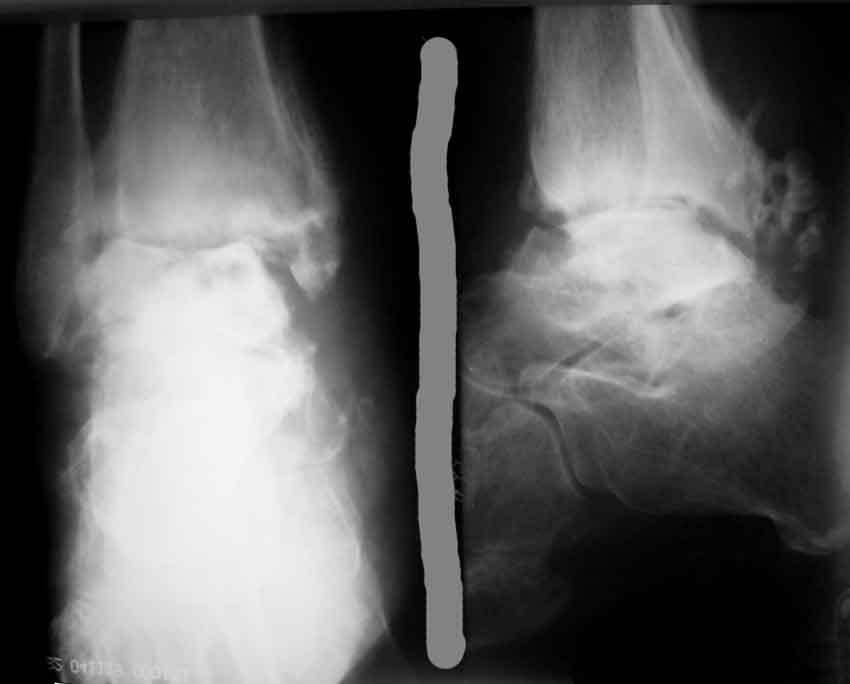

Коллеги! Хочется вынести на обсуждения ортофорума вопрос: - Как лечить асептический некроз таранной кости? Пациент Е., 52 года, Обратился в связи с болями при нагрузке в правом голеностопном суставе, ограничение движений.Травма 26.06.2004 в результате падения с высоты(прыгнул с лестницы). Лечился стационарно с диагнозом закрытый перелом правой таранной кости, обеих лодыжек со смещением. Выполнено оперативное лечение - остеосинтез лодыжки спицами, гипс. В сентябре 2004 спицы удалены. В сентябре 2004 острый правосторонний илеофеморальный тромбоз. Проведен курс консервативной терапии. В мае 2005 года больному проводился курс стационарного консервативного лечения по поводу посттравматического артроз правого голеностопного сустава. В ноябре 2005 года повторное ухудшение состояния, усиление болей повторный курс консервативного лечения в диагноз добавлен посттромбофлебитический синдром. ХВН 3А ст правой нижней конечности. В приложении R- до удаления спиц и последние R-граммы. C ув. Коробушкин Г.В.,РГМУ, Москва